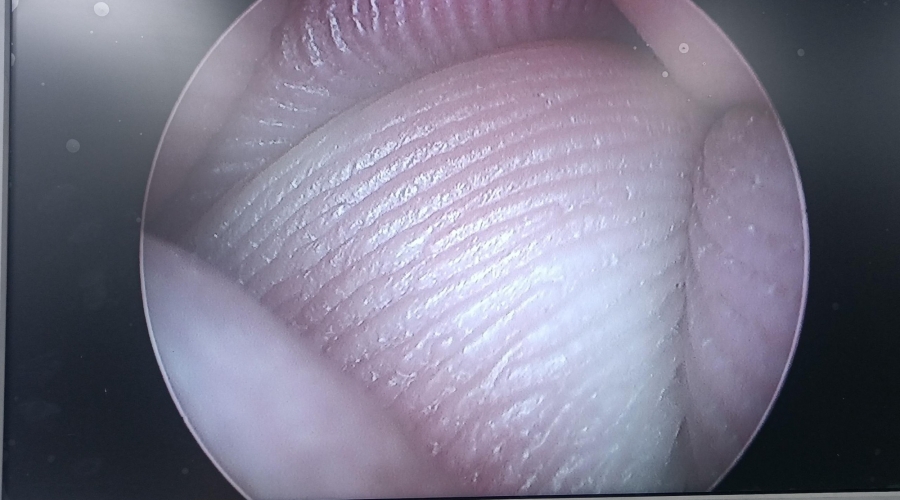

設備型號Wolf狼牌電切鏡8650.414

故障內容圖像模糊,棒透鏡破碎,導光錐破碎,目鏡罩破碎,鏡身有磕碰,但不影響使用。

維修方案更換棒透鏡、導光錐、目鏡罩,校對圖像,內窺鏡抗震蕩抗沖擊性能測試,內窺鏡密封性性能檢測;內窺鏡抗震蕩性能測試,內窺鏡冷熱沖擊性能檢測。